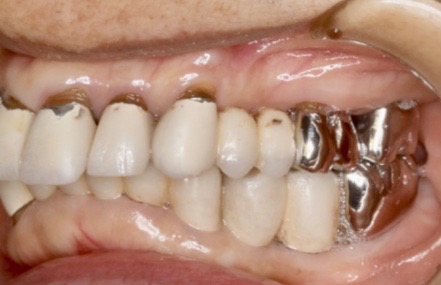

下記の症例は骨幅が薄く、このままでは長期的に安定したインプラント治療が不可能だったので、抜歯と同時に骨造成(GBR)を行い、その後歯肉移植(FGG)を行い、術後安定した経過を辿るよう配慮致しました。